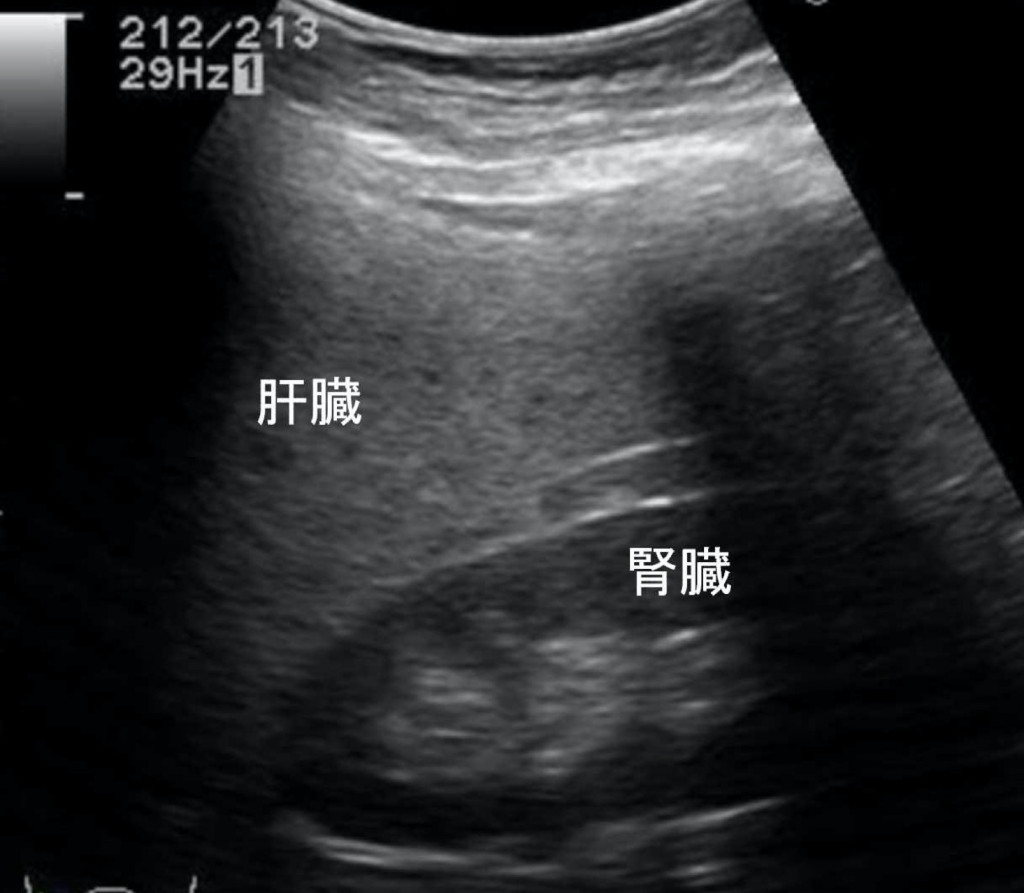

肝臓を占拠する!!パート1~できもの 悪くないもの 」腹部超音波検査 Vol.3 – みどり病院神戸市、明石市、循環器、透析。